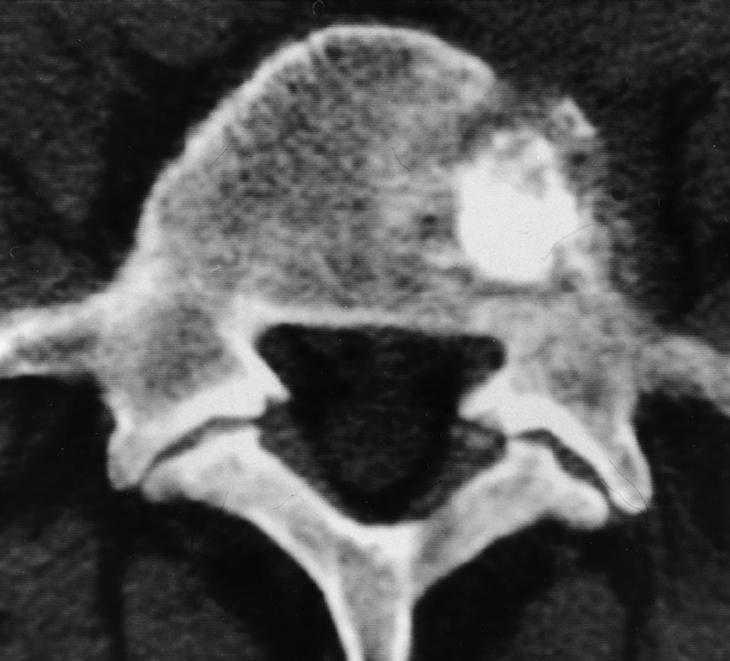

Los controles radiológicos de la vertebroplastia se realizan con radiología simple (fig. 1) y con TC (figs. 2A y 2B).

En una lesión vertebral, la TC revela una lesión hipodensa, osteolítica que afecta fundamentalmente al cuerpo vertebral respetando los pedículos. En muchas ocasiones se puede observar gran extensión hacia el espacio paravertebral y epidural. La TC descarta la existencia de calcificaciones intratumorales.

En la radiografía el hemangioma presenta características estriaciones óseas groseras y verticales en el cuerpo vertebral separadas por zonas radiolúcidas. En TC las estriaciones groseras se presentan en forma de imágenes puntiformes hiperdensas dentro de un área de rarefacción ósea. En RM el hemangioma se presenta como una lesión hiperintensa en las secuencias potenciadas en T1 y T2. El aumento de señal en T1 es debido al componente graso de la lesión, mientras que la hiperintensidad en T2 es debida al componente vascular.